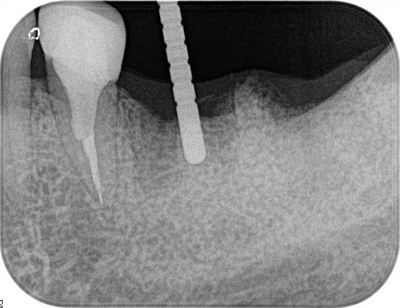

オペ終了時のレントゲン写真です。

O・Kさん、オペおつかれさまでした。